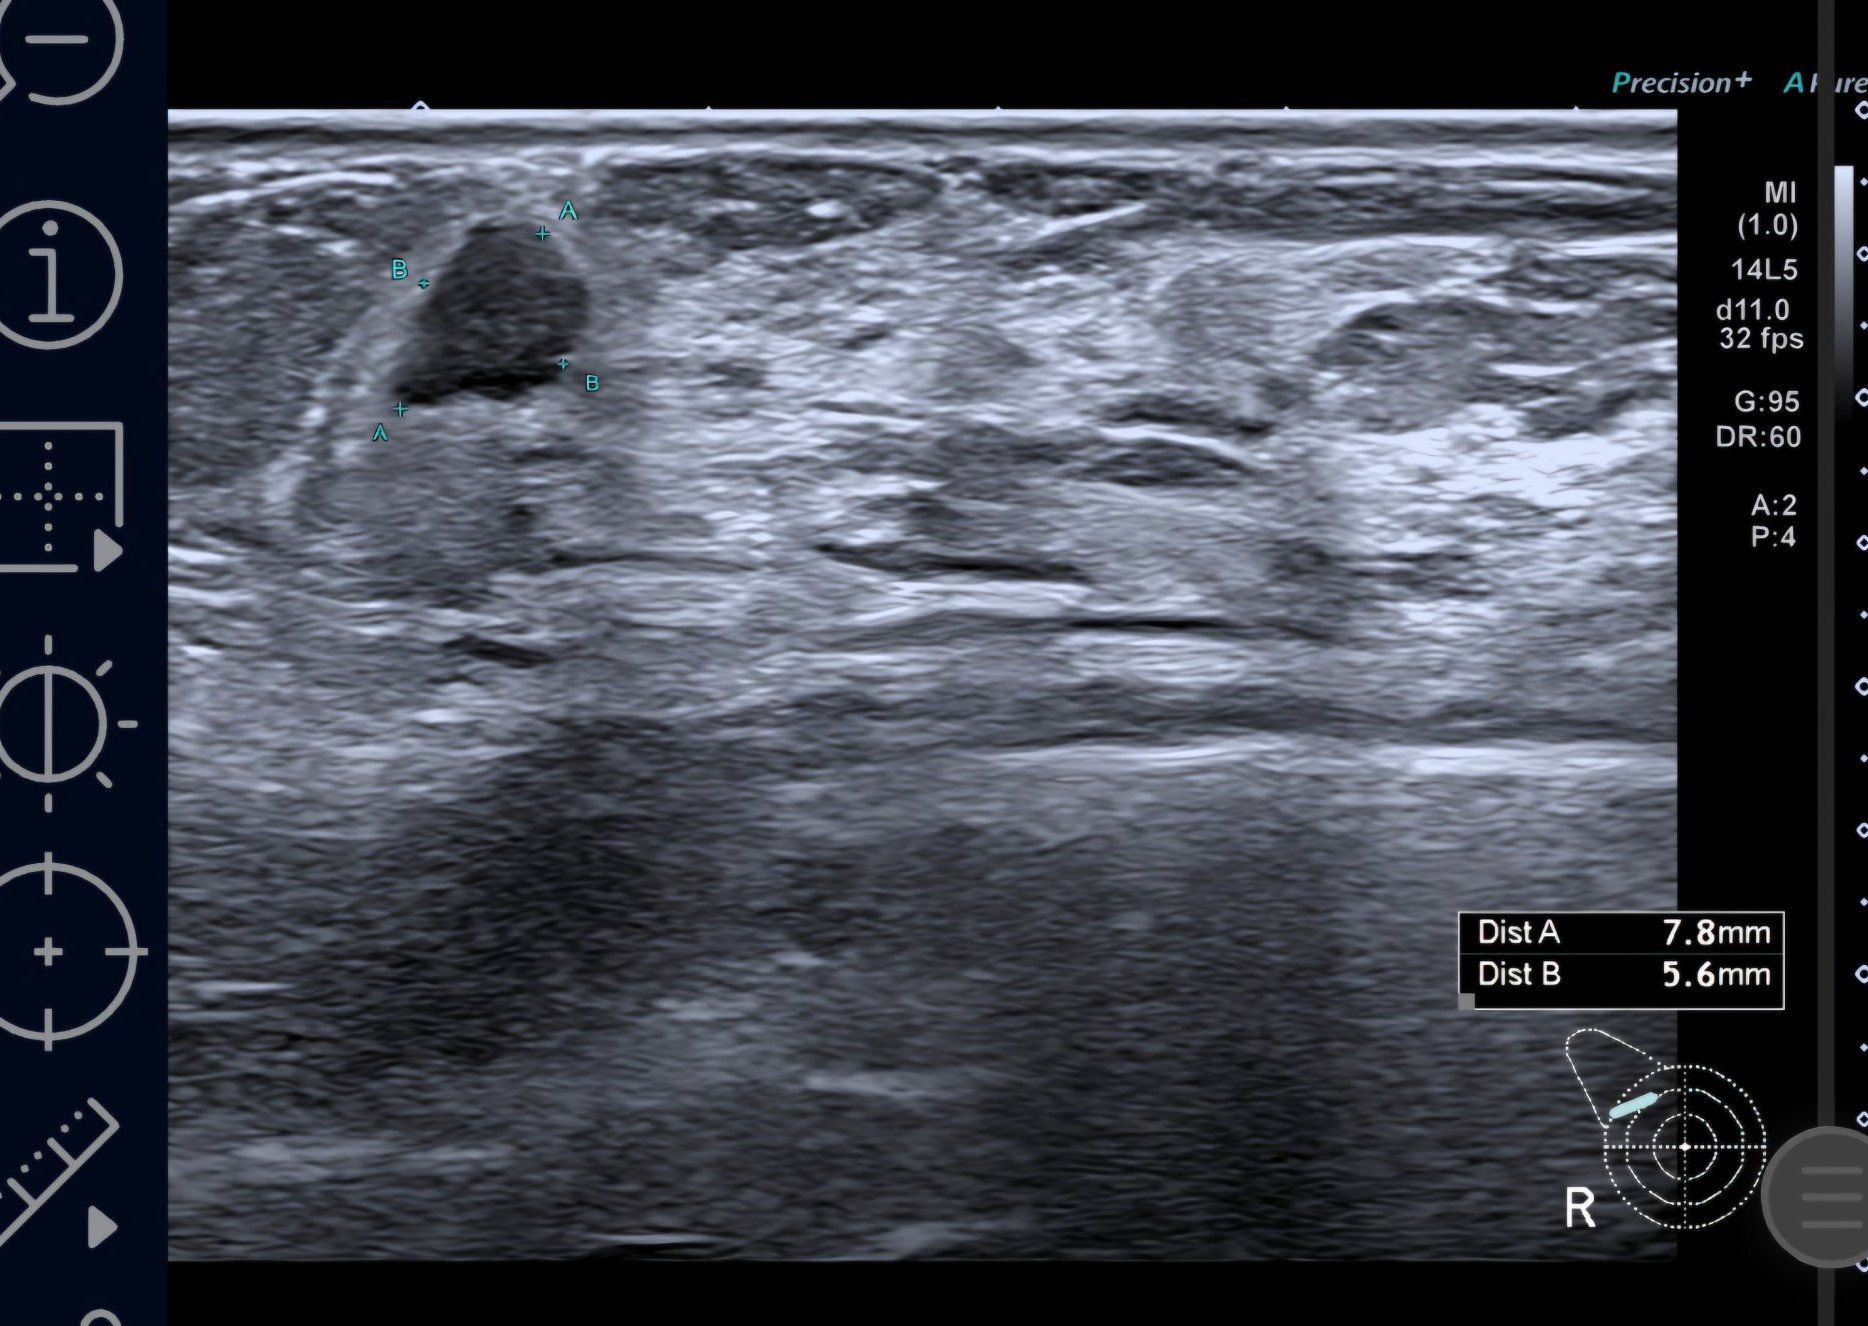

Далинда, ето малко картинки от BIRADS 4c ( най- вече вляво) , само по образни. Това са първите картинки, оттогава имам още нови попълнения. Биопсията не показа точно какво е и какво не е, според лекарите може би не са "уцелили" точното място в лезията, защото има известно разминаване. Вчера бях на ПЕТ, само сумтяха и ми казаха, че ще разбера резултатите от лекуващата другата седмица, след като е минала Туморната комисия 🤷‍♀️

Marie curie, твоето само по формата и е силно подозрително за рак. Неправилни, наръбени форми са червена лампа.